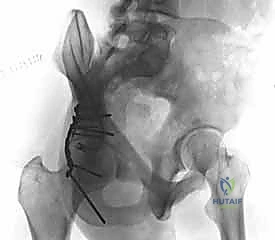

Page 40 of 47Thumb Carpometacarpal Joint Arthroplasty: An Intraoperative Masterclass in Resurfacing and Total Joint Replacement

- Mastering Silicone Arthroplasty for MCP and PIP Joints: An Intraoperative Guide

- Thumb Carpometacarpal Joint Ligament Stabilization: An Operative Masterclass

- Mastering Thumb CMC Resection Arthroplasty with FCR Suspensionplasty